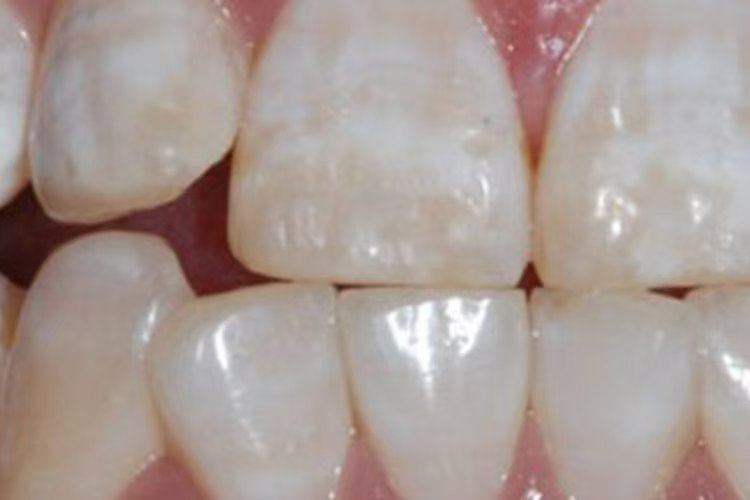

1.轻度(白垩型): 牙面上出现不透明的黄白相间的斑块或条纹,表面粗糙。